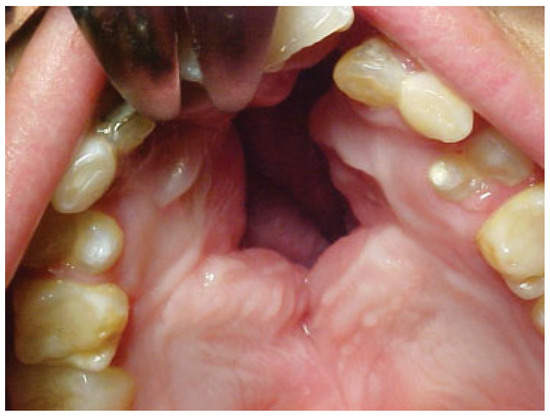

Case 9

A 7-year-old boy with a history of bilateral cleft lip and palate presented with an anterior fistula measuring 40 × 28 mm after palatal surgery (Figure 11). The fistula was closed with a left anteriorly based NAMMC flap (Figure 12, Figure 13 and Figure 14).

Figure 11. Severe fistula located on the hard palate after primary palatoplasty in an 8-year-old patient with isolated cleft palate.

Figure 12. Postoperative (1 month) view of the patient in Figure 11 after closure of the fistula using a posteriorly based nasal artery musculomucosal cutaneous flap.

Figure 13. Postoperative view of the patient in Figure 11 and Figure 12 1 year after surgery when the patient returned for soft palate repair.